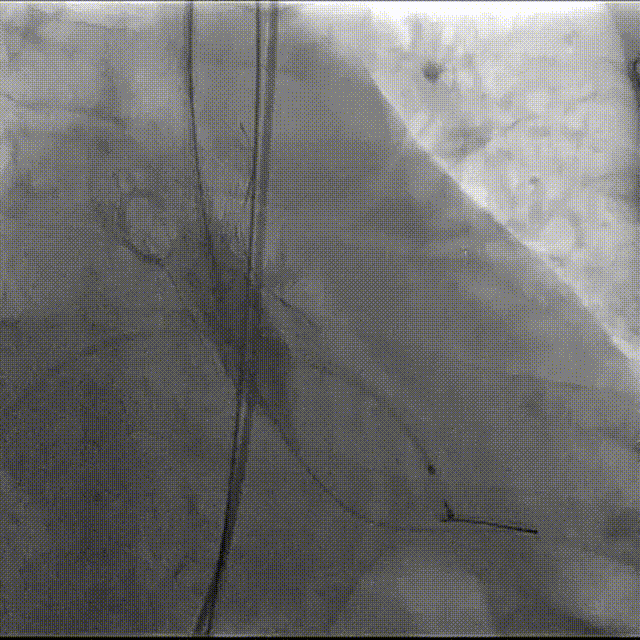

主动脉根部造影

最终造影